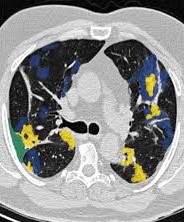

Segmentation d'images Covid-19

Sidi Mahmoudi

Coming Soon ...